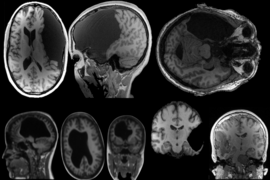

Over a decade ago, the neuroscientist Ev Fedorenko asked 48 English speakers to complete tasks like reading sentences, recalling information, solving math problems, and listening to music. As they did this, she scanned their brains using functional magnetic resonance imaging to see which circuits were activated. If, as linguists have proposed for decades, language is connected to thought in the human brain, then the language processing regions would be activated even during nonlinguistic tasks.

Fedorenko's experiment, published in 2011 in the Proceedings of the National Academy of Sciences, showed that when it comes to arithmetic, musical processing, general working memory, and other nonlinguistic tasks, language regions of the human brain showed no response. Contrary to what many linguistists have claimed, complex thought and language are separate things. One does not require the other. "We have this highly specialized place in the brain that doesn't respond to other activities," says Fedorenko, who is an associate professor at the Department of Brain and Cognitive Sciences (BCS) and the McGovern Institute for Brain Research. "It's not true that thought critically needs language."